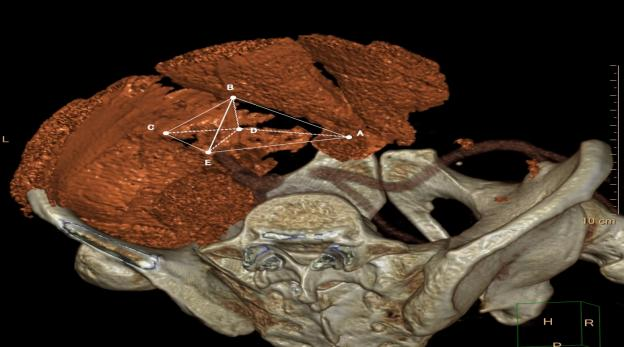

2020年12月王峰于World Journal of Clinical Cases发表“Application of computer tomography-based 3D reconstruction technique in hernia repair surgery”的研究论文���。该研究探讨多层螺旋CT三维重建和解剖学测定肌耻骨孔数据的相关性����,通过研究找到一种术前收集个体化肌耻骨孔数据的方法����,为修补材料的制作提供精准的数据支持���,力图制作出适宜每一个个体解剖构造的3D生物补片��。

该研究术前应用Phillips公司Brilliance256层iCT对所选患者行腹部盆腔CT扫描��,所得数据传入EBW工作站进行自动重建并生成三维VR��,调整VR角度寻找最适标记点测量距离并记录数据���;再于术中暴露肌耻骨孔区域各标记点用消毒软尺测量距离并记录数据���。应用SPSS 20.0统计学软件对两组数据进行配对样本的t检验����,P>0.05��,无统计学差异����,说明手术前后测量的数据基本一致����。证实术前应用多层螺旋CT三维重建技术���,可以准确地获得肌耻骨孔区各标记点的数据及相互关系����,能够为3D打印生物补片的制作提供精确的数据信息����。